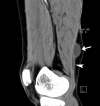

Intratendinous ganglion cyst is a very rare lesion with an unknown aetiology that originates within the tendon. We encountered a case of 43-year-old woman who complained of a palpable, non-tender mass in the thigh with increasing swelling. An intratendinous ganglion cyst in the semimembranosus tendon of the lower extremity was diagnosed and located by ultrasound and MRI. Nine months after a surgical excision, there were recurrent ganglion cysts along the semimembranosus tendon. We describe this case with a review of the relevant literature.